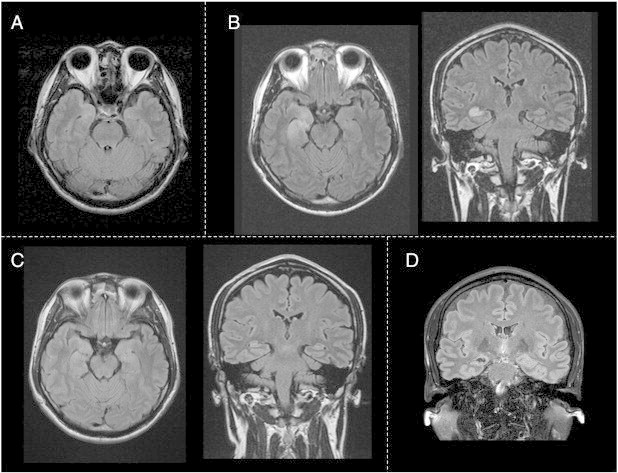

Fig. 1.

FLAIR images of MRI (A) at onset, (B) one month after onset (seizure frequency was 10 per day), (C) three months after onset (seizure-free), and (D) one year after onset (continuously seizure-free).

Fluid-attenuated inversion recovery (FLAIR) images of brain MRI showed high intensity in the right hippocampus, right uncus, right amygdala, and swollen right hippocampus (Fig. 1B). Subsequent [18F] fluorodeoxyglucose-positron emission tomography scan and N-isopropyl-p-[I123] iodoamphetamine single-photon emission computed tomography showed hypometabolism and hypoperfusion in the right mesial temporal lobe.

Two months after the cessation of seizures, the lesion indicated by the high intensity of the FLAIR images on MRI was improved (Fig. 1C). Only when he forgot to take carbamazepine did he feel chills again but no goose bumps appeared. His seizures have been well controlled, and his work as a computer programmer has progressed with no difficulties. However, one year after, his right hippocampus was revealed to be atrophic on MRI (Fig. 1D).

Imaging findings associated with epileptic seizures might reflect many physiologic changes, including vasogenic edema, demyelination, and astrocytosis. Long-term observations of these transient alterations revealed that 33–40% were associated with long-term development of regional cerebral atrophy or hippocampal sclerosis [14,16]. The case presented herein also showed atrophy in the right hippocampus on MRI images after one year, despite temporary improvement as indicated by the high intensity of the FLAIR images after becoming seizure-free. Long-term follow-up MRI might be important for such cases. We must, therefore, devote attention to the fact that recurrent autonomic seizures might injure the hippocampus and produce hippocampal atrophy, although it is difficult to exclude the possibility that the hippocampal changes are the result of an inflammatory process.